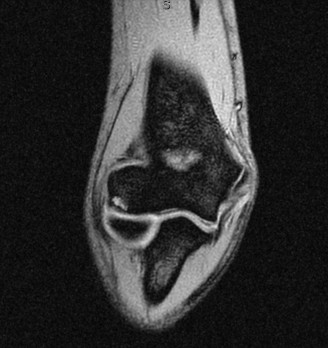

>25%, a bony stabilization procedure is necessary. In the 15% to 25% range, opinions vary, and one must exercise clinical judgment. Specific treatment options are further discussed in Table 2–1. Additional Questions An 18-year-old male with a history of recurrent anterior instability is seeking surgical treatment after having failed a course of extensive PT. His examination demonstrates a Grade 2 load and shift test and positive sulcus sign. His MRA is

shown in Fig. 2–35.

Figure 2–35

The correct answer is (E). The question stem describes recurrent anterior instability that has failed conservative treatment and hence necessitates surgical intervention. Several surgical procedures have been described for anterior instability. In the absence of significant bone loss, the most common procedure utilized is an arthroscopic Bankart repair and capsular shift. The image provided does not demonstrate any significant bone loss, making this the correct answer. An isolated Bankart repair (Answer D) will restore the bumper effect that an intact labrum provides but will not restore the sling effect of the normal anterior capsule. A Bristow procedure (Answer B) would be appropriate in the setting of significant anterior glenoid bone loss. The other procedures represent nonanatomic procedures that are largely historical.